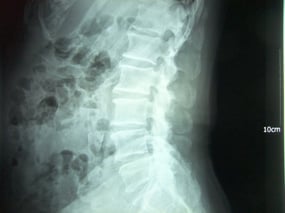

レントゲン検査の結果を見て、整形の先生の見解は「骨が変形していて間も狭くなっているので歩くのは控えて」ということでした。

私は、疑問に感じたので後日、レントゲン画像を見せてもらいに病院に足を運んだ。

確かに多少の変形はあるものの、年相応の退行性の変形であり、関節の間も比較的しっかりしていると判断し、父には気にしなくて良いので、今まで通りにウオーキングの継続を勧めた。